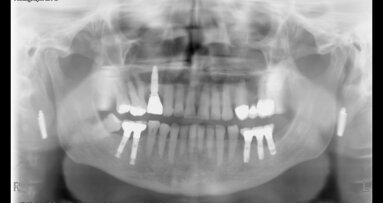

Pro účely statistické analýzy byly použity univariační regresní modely ve vztahu jak k implantátům tak pacientům. Celkem bylo zkontrolováno 460 krátkých implantátů, v délkách od 4 do 9 mm, použitých u 199 pacientů a sledovaných až po dobu devíti let. Míra zachování krátkých implantátů byla 95,86 procenta a 92,96 procenta a úspěšnost 90,00 procenta a 83,41 procenta, hodnoceno vzhledem k počtu implantátů a zúčastněných pacientů. Periimplantitida byla hlášena jako příčina selhání krátkého zubního implantátu v 73,91 % případů. Univariační regresní modely odhalily nižší úspěšnost při implantaci u ženského pohlaví. Kromě toho bylo zjištěno, že kouření a periodontitida v anamnéze mají významný negativní vliv na přijetí krátkých implantátů, posuzováno ve vztahu k implantátům i pacientům.

Tyto výsledky podporují použití krátkých implantátů jako předvídatelné možnosti dlouhodobé léčby. Kouření a periodontitida v anamnéze jsou však považovány za potenciální rizikové faktory pro úspěšnost krátkých implantátů. Podle vědců jsou tyto výsledky v souladu se závěry jiných dlouhodobých studií.